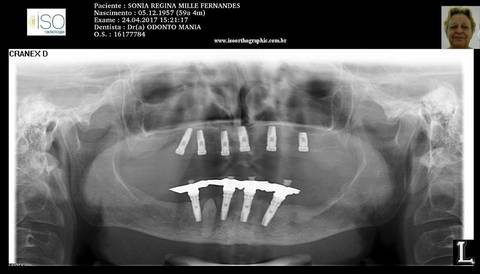

PRÓTESE TOTAL FIXA EM IMPLANTES

S.R.M.F